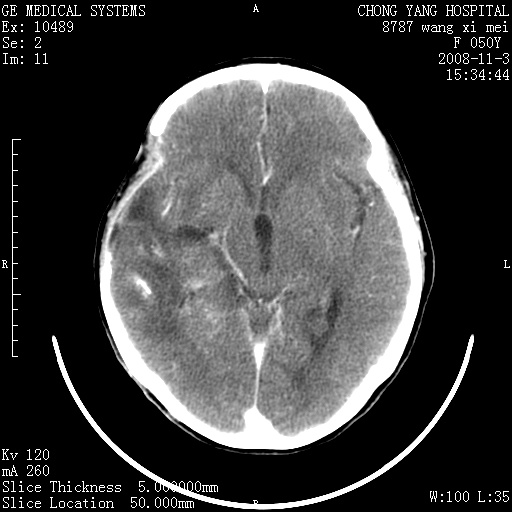

标题: CT16469:女,50岁,胶质瘤术后6年,今平扫加增强,请大家帮 [打印本页]

标题: CT16469:女,50岁,胶质瘤术后6年,今平扫加增强,请大家帮

右侧颞顶部可见低密度实变影,内见不规则钙化灶,边界不清,占位效应明显,侧脑室后角受压移位,符合胶质瘤术后复发改变。

右颞骨局限性缺如,局部脑组织无外隆。右颞叶可见片状脑脊液样低密度影,边缘较清,右侧侧脑室三角区可见一块状等密度影,且伴有强化,余未见明显异常改变。

考虑:右大脑术后改变伴肿瘤复发。

手术后局部片状低密度改变(软化灶),其后方颞叶似等密度病灶,界限不清,内见钙化,有轻度占位效应,但增强后强化之血管走行如常。应不考虑:复发!

考虑右侧颞顶叶胶质瘤术后复发。

应考虑肿瘤复发,右颞顶叶已出现轻度强化肿块.必要时可与原片比较以下.

右侧颞顶部混杂密度影,内有钙化,有占位效应。应该是复发灶。结合术后片更好。